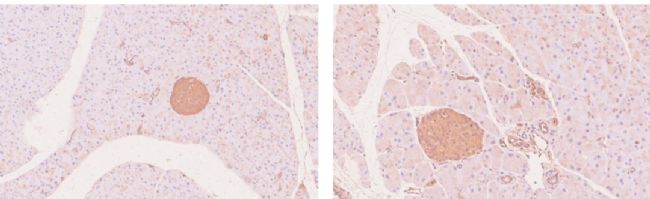

(2) 免疫組化檢測

野生型小鼠(WT, 左)和 B6-hGLP-1R 小鼠(右)胰腺免疫組化染色。結果顯示在B6-hGLP-1R小鼠的胰島中特異分布著人源GLP-1R的表達。